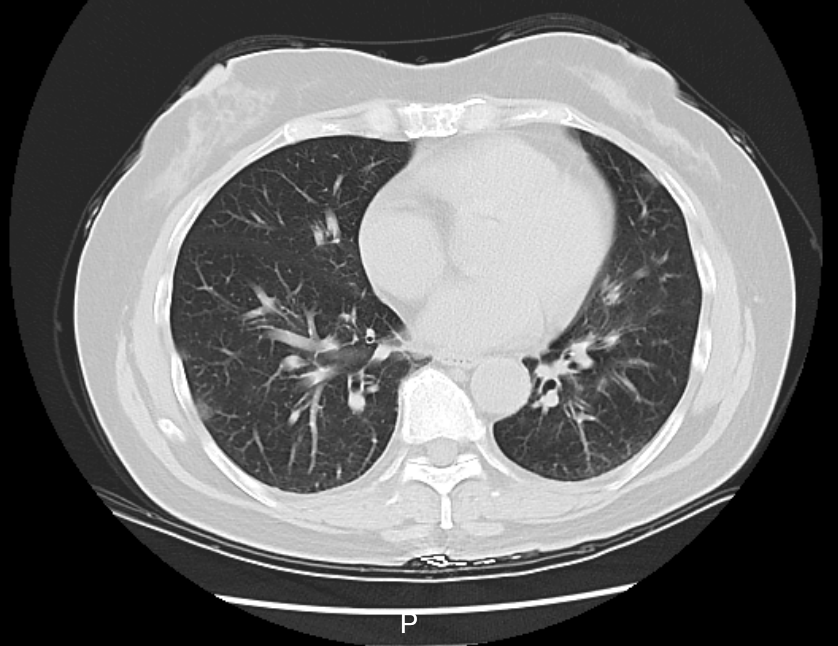

“Chúng tôi mới đi du lịch một tuần trước. Sau khi trở về, tôi bắt đầu xuất hiện các triệu chứng sốt, ho, đau họng và đau nhức cơ thể. Tôi đã chịu đựng triệu chứng này trong vài ngày nhưng đến hôm kia, do không thể tiếp tục chịu đựng nên tôi đã nhanh chóng đến bệnh viện địa phương để chụp X-quang lồng ngực. Các bác sĩ cho biết tôi bị biến chứng viêm phổi và khuyên nên nhập viện ngay” – Cô Lý (50 tuổi, đã thay đổi tên) lấy tờ báo cáo chụp X-quang có dòng chữ “viêm phổi góc dưới bên trái” với các vết trắng phổi cho hay.

Kết quả xét nghiệm cho thấy, cô Lý cùng gia đình đều dương tính với virus cúm A và riêng cô Lý đã biến chứng viêm phổi. Sau 2 ngày điều trị, thân nhiệt của cô Lý đã trở lại bình thường và các triệu chứng như ho, đau họng cũng cải thiện đáng kể.